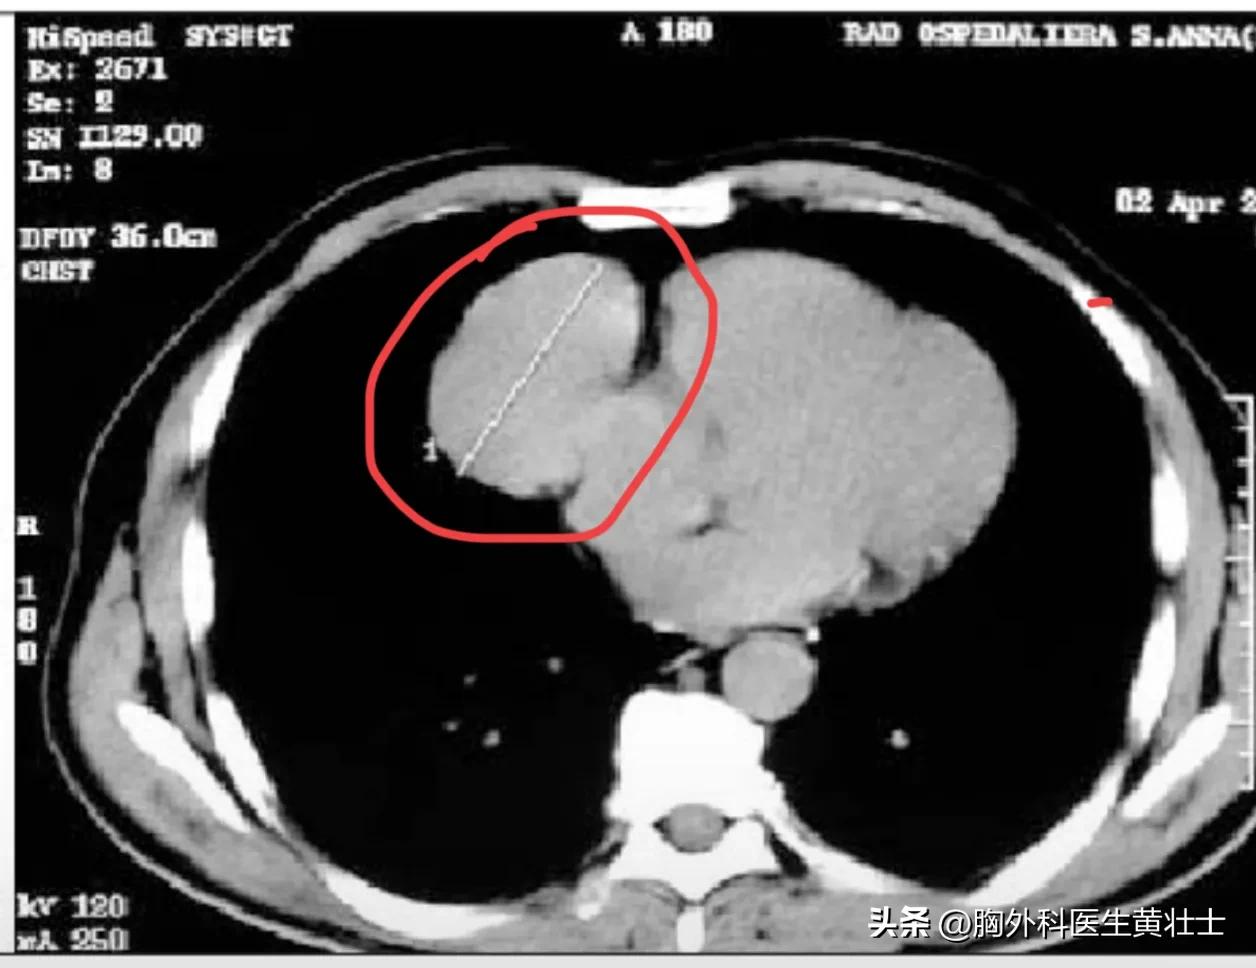

异位到中纵隔的胸腺瘤(红色圈内)

异位胸腺瘤的形态多样,可能为单发、或多发的囊性、实性或混合性肿块;也可能是微小的散在结节。

异位胸腺瘤的诊断需要结合影像学检查和组织学检查。其中,CT和MRI可以帮助确定异位胸腺瘤的位置、大小和形态;而组织学检查则可以确定异位胸腺瘤的病理类型。